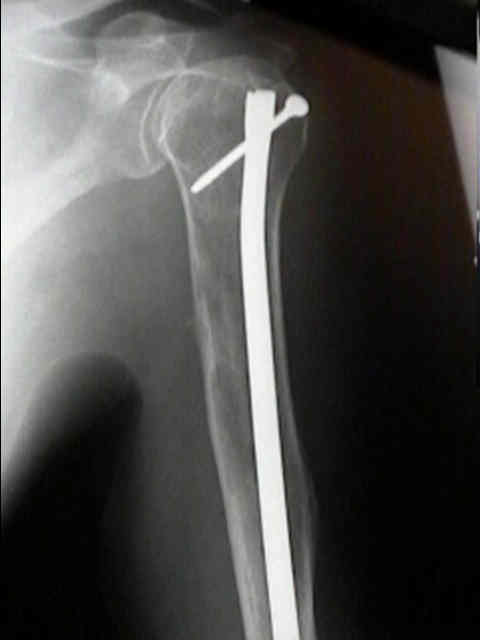

Se localiza, preferentemente, en los huesos donde existe médula ósea roja: vértebras, costillas, esternón, pelvis, cráneo y huesos largos (tercio proximal fémur y húmero).

Las fracturas patológicas de columna o fémur pueden ser el primer

síntoma. Se producen con un traumatismo mínimo o incluso sin trauma.

Radiográficos:

Las radiografías normales pueden mostrar osteopenia difusa.

"Lesiones perforadas" o en "sacabocado" sin ninguna formación de nuevo-hueso circundante. Su diámetro es variable (hasta 5 cm.), redondas y múltiples.

Con el tiempo las lesiones pueden cambiar de osteopenia difusa a más permeativa con patrón destructivo apolillado, y a veces con expansión cortical.

La destrucción del hueso ocurre con poca o ninguna formación de hueso reactivo a menos que haya una fractura patológica.

Fijación

quirúrgica:

El enclavado IM femoral profiláctico: